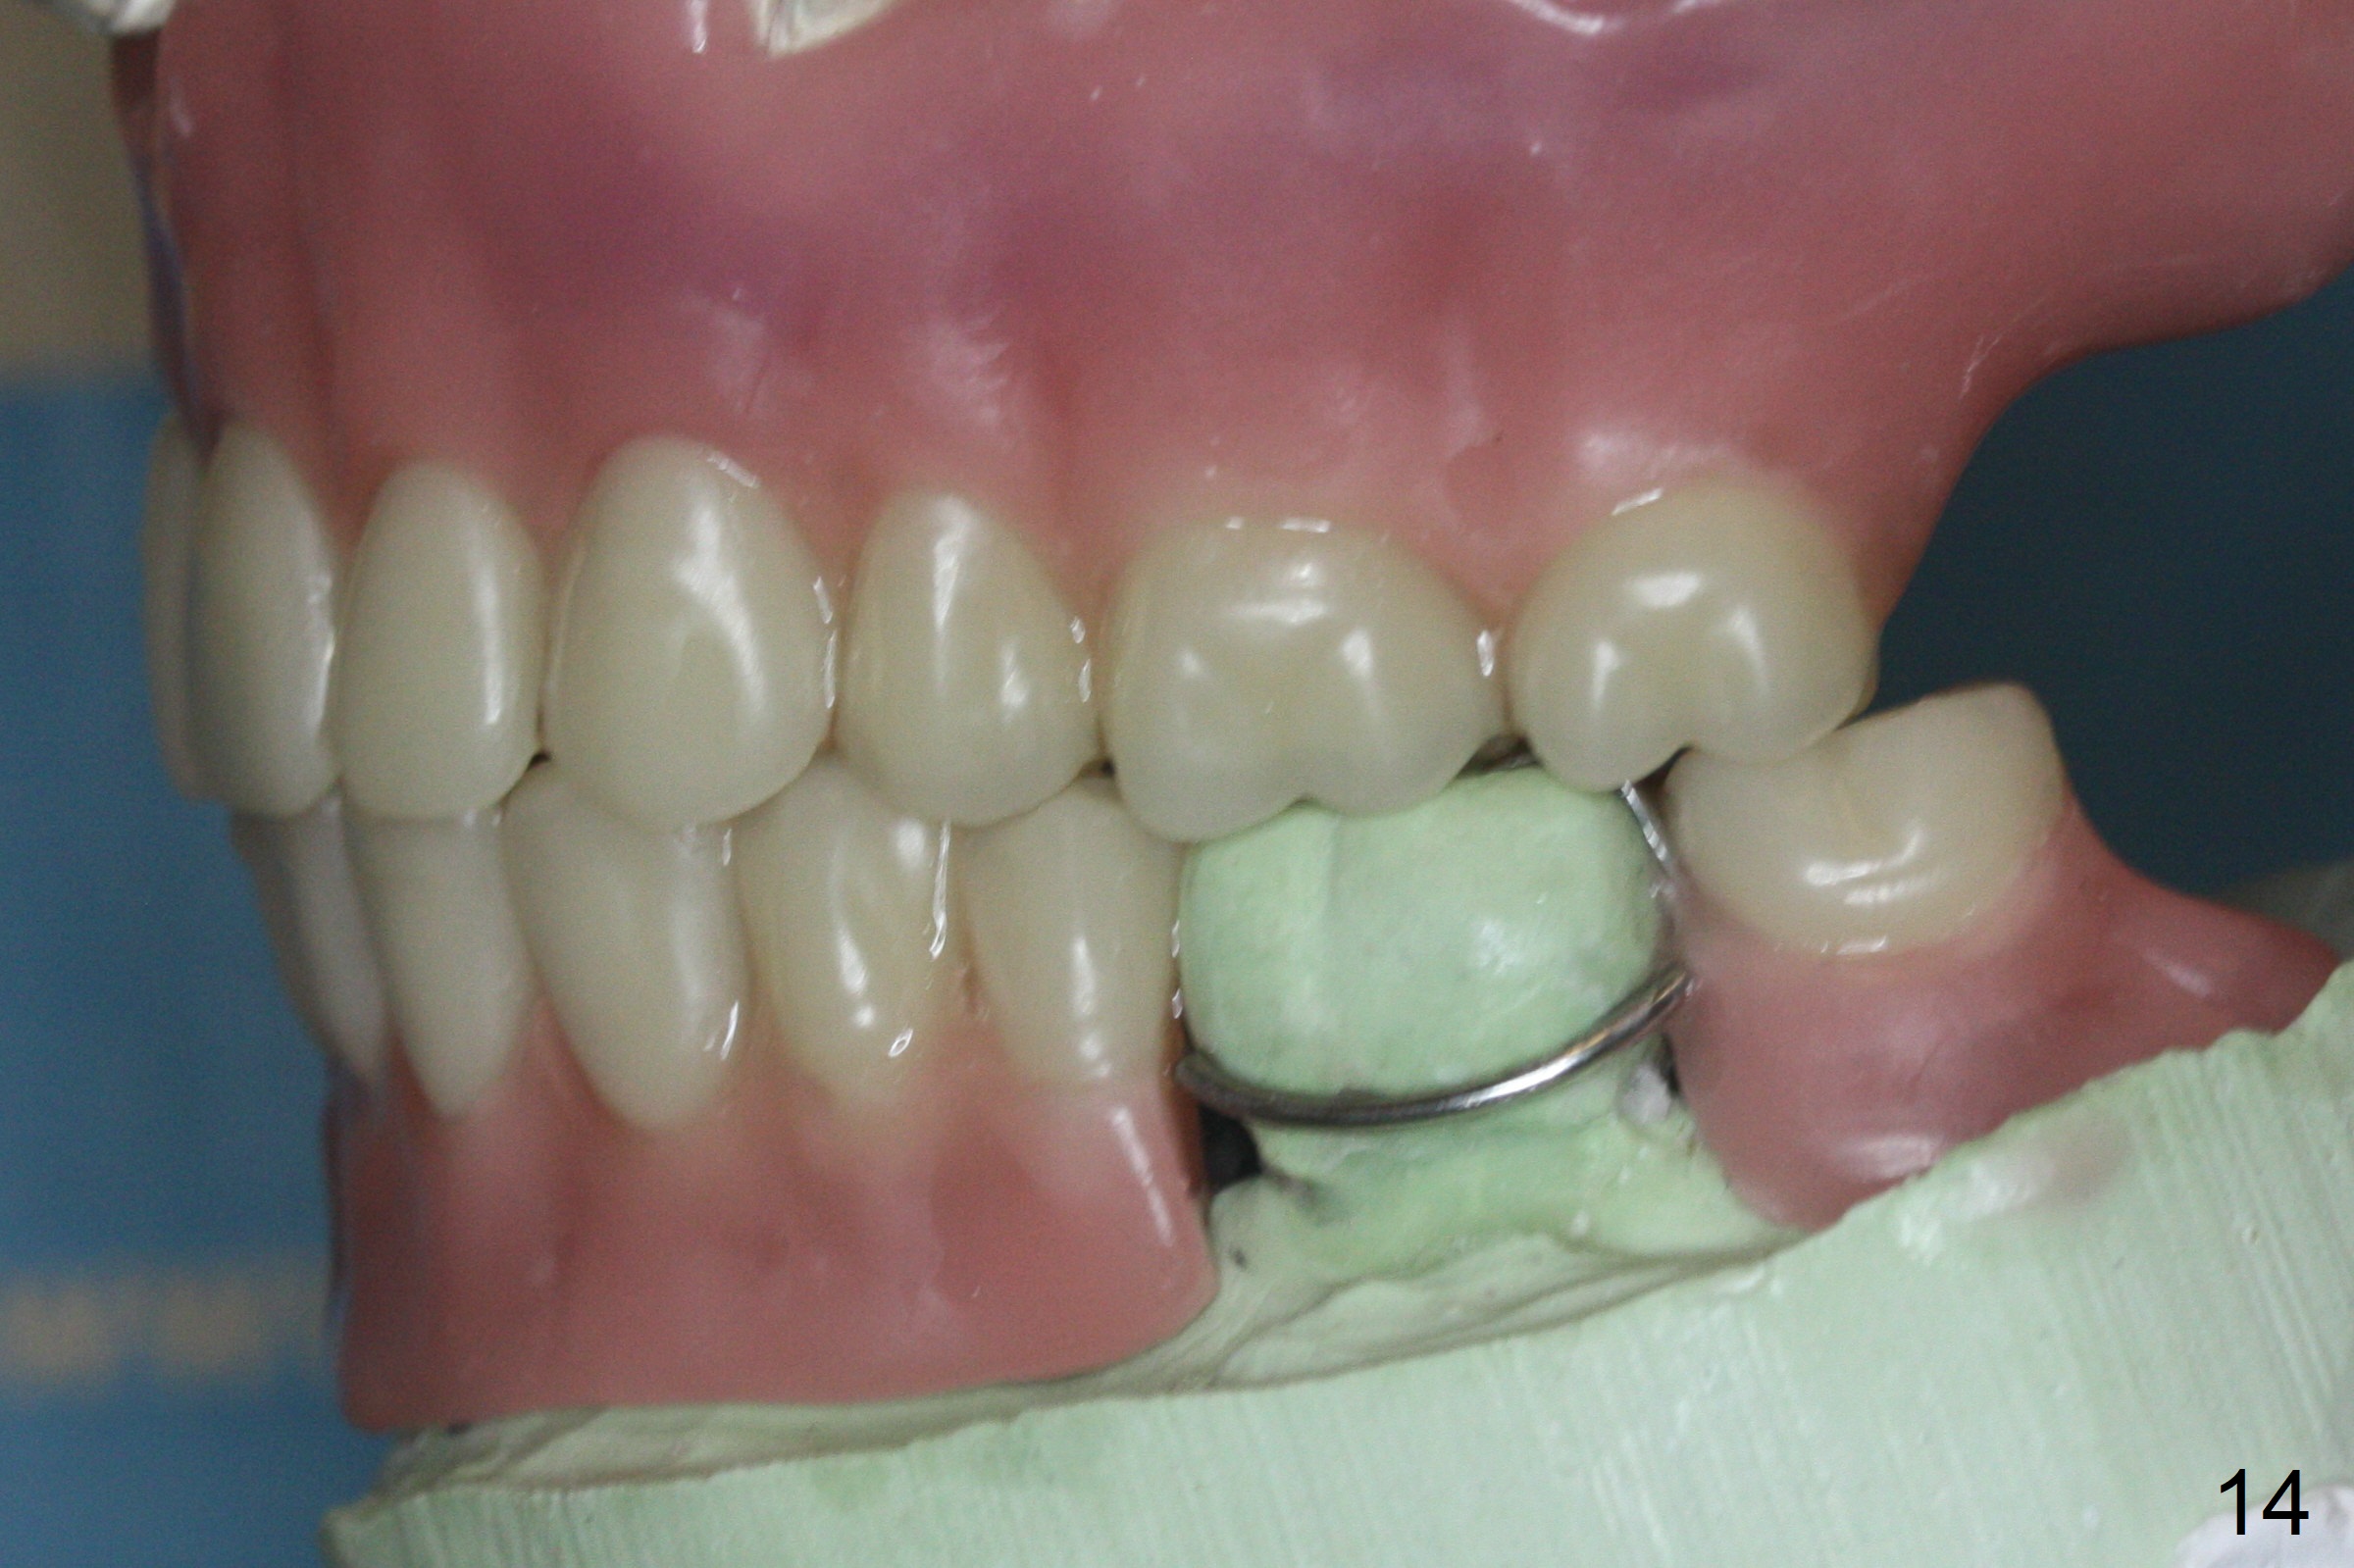

The implant osteointegrates 2 months postop (Fig.9). A pair abutment is placed (Fig.10: 5x4(2) mm) for a provisional (Fig.11). Wax up for final restorations (Fig.12-15). There is no bone resorption 1 year 4 months post cementation (Fig.16). The RPD is doing fine. The implant remains stable 3.5 years post cementation (in spite of open margin), while the other abutment for the RPD (the tooth #30) has mobility with gingival recession.